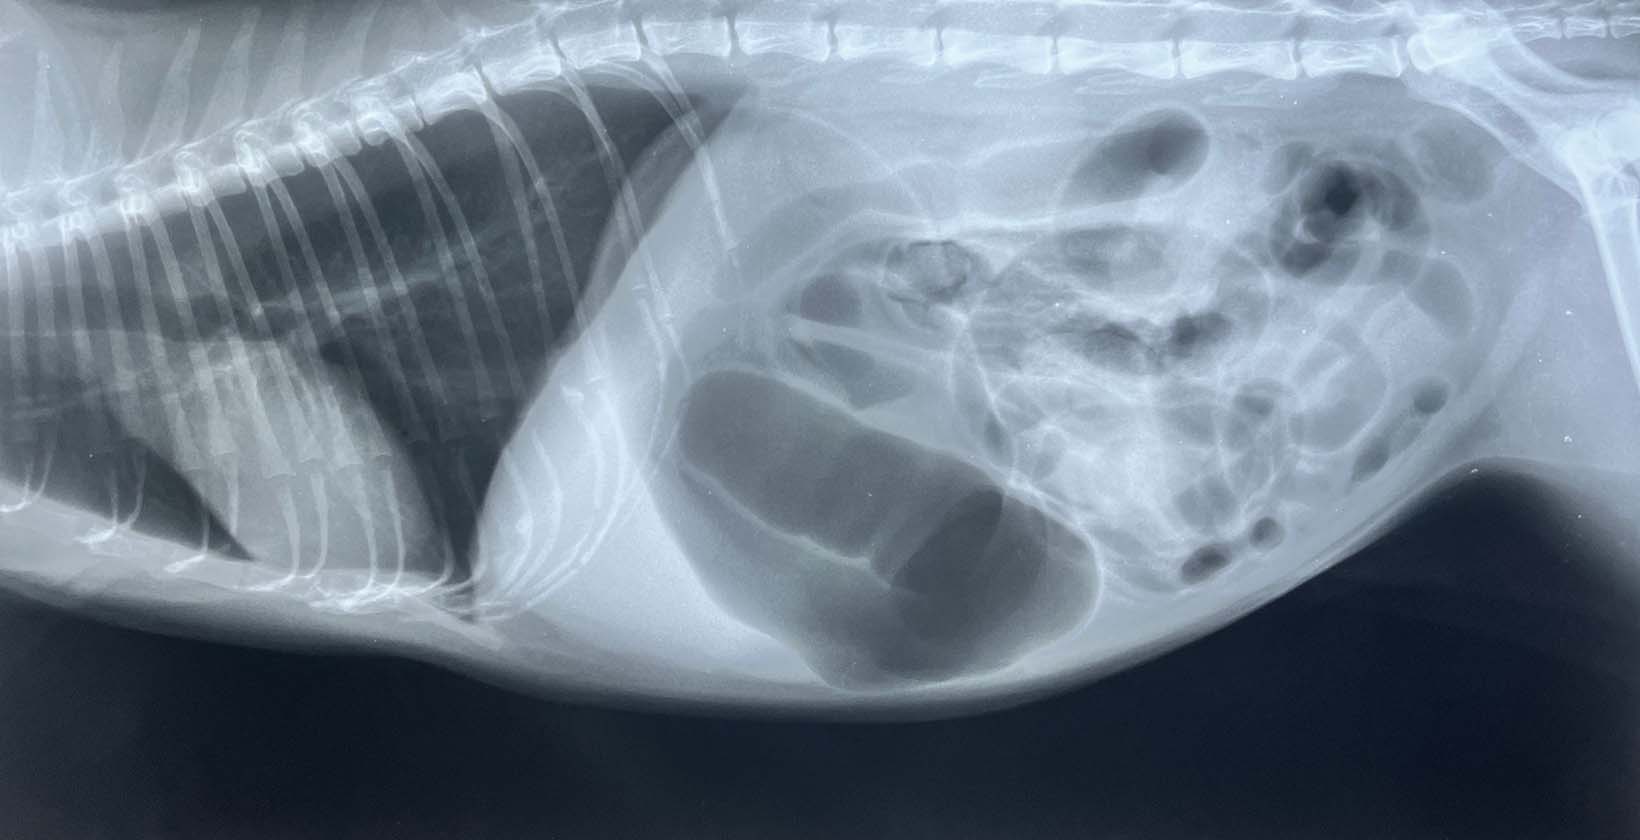

- Canine Osteoarthritis: Osteoarthritis in dogs is a progressive, inflammatory, and painful joint condition. Arthritic dogs have trouble moving due to joint aches and refuse to walk when the pain gets too much. Pain control and regular use of joint-friendly supplements help with the problem. CBD oil for dogs relieves arthritis pain and increases mobility.

- Hip or Elbow Dysplasia: Hip dysplasia is an orthopedic condition in which the dog’s hip socket and the thigh bone’s ball-shaped head do not fit properly, causing pain. Elbow dysplasia is a similar problem affecting the elbow joint. Dogs with hip or elbow dysplasia are reluctant to walk due to pain.

- Painful Injuries: Injuries on a dog’s legs and paws are painful and cause unwillingness to walk or go outside. Muscle sprains and strains are common in dogs, same as paw cuts, paw burns, thorn nails, and ingrown nails.

Canine arthritis and dog headaches are frequently reported as painful health conditions resulting in a reluctance to go outside. Dogs with arthritis are in pain when walking, while headaches are triggered or worsened by bright light and loud noises.

Sometimes, a dog doesn’t want to go outside due to medical conditions. For example, an older dog with arthritis refuses to leave the house because going outside is associated with walking, which puts pressure on the already achy joints.

Arthritis in dogs manifests with signs such as a reluctance to jump up and down furniture or climb stairs and licking the joints.